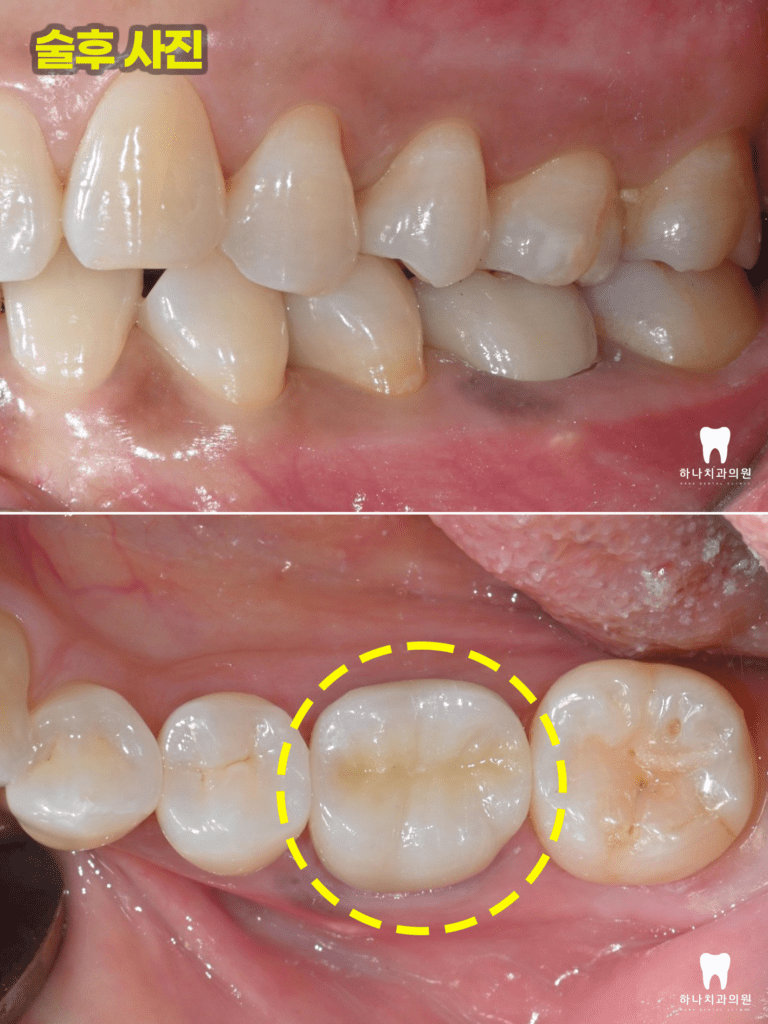

4회에 걸쳐진 치료를 완료하고

근관의 완전한 확보, 세척, 충전을

완료한 뒤 마무리 후 본뜨기 전의 모습입니다.